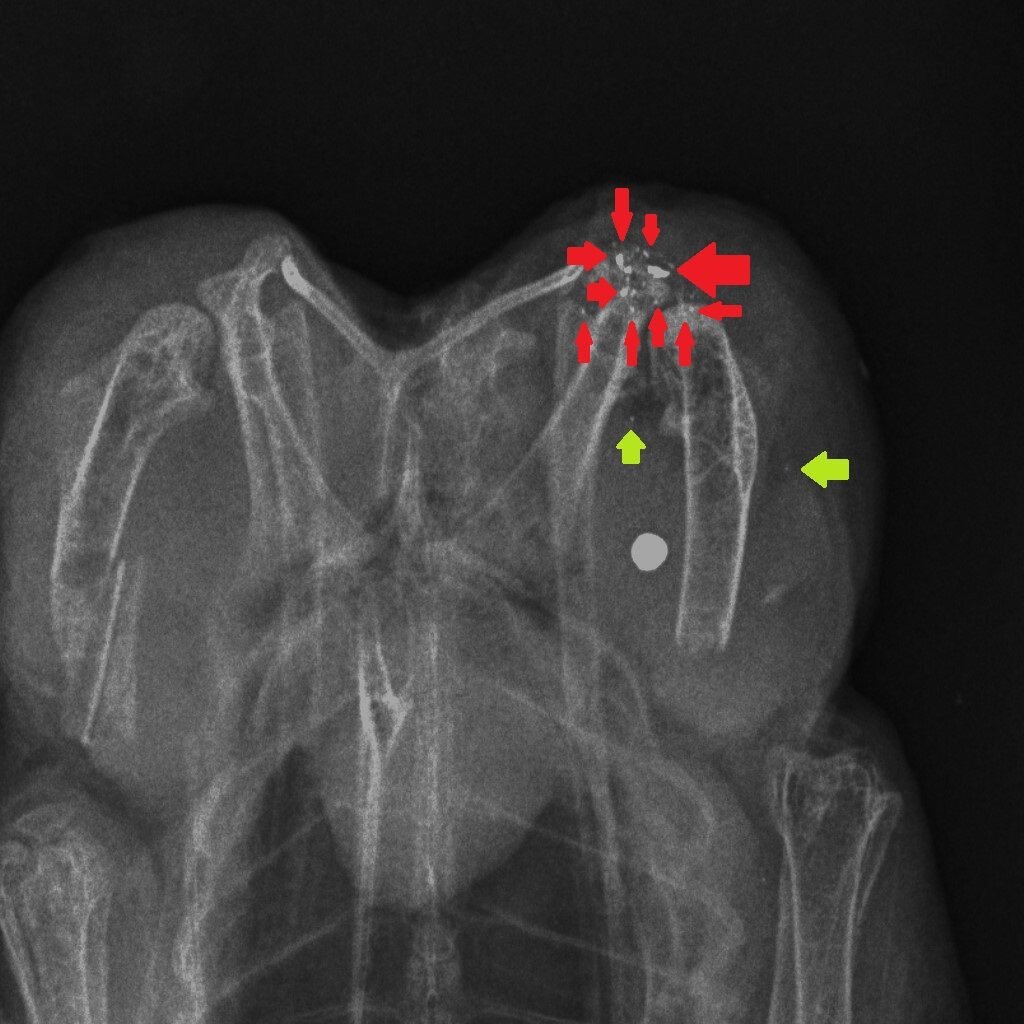

How could we reduce the risk of exposure to lead in game meat? It’s simple – stop shooting lead ammunition into animals that are destined for the human food chain. One of the useful properties of lead is that it is soft and malleable – that’s why, in the past, we have used it widely. But those same physical properties mean that lead passing through the flesh of a shot animal, hitting organs, soft tissue, bones and cartilage, shatters and tiny fragments of lead spread through the body of the animal. Here are three x-rays of shot birds that were bought in butcher’s shops and then x-rayed. The top x-ray is of a partridge and the other two are Red Grouse. Large white circular objects are lead shot. The green arrows point to fragments of bone and the red arrows indicate fragments of lead, from the shot, that have spread through the flesh.

Almost all of the fragments of lead are tiny – far too small to be detected in the cooking or eating process. Yes, you can spit out the almost-intact lead shot but you can’t get rid of the fragments. The lead analyses that have been done in studies cited above, and in our own, remove the lead shot and analyse the lead content of the meat after that removal. So when Sainsbury’s say that their game meat has no lead shot in it that’s good (although careful eating would remove those anyway) but they are not removing the tiny fragments of lead. So removing the almost intact lead shot particles is pretty irrelevant to the lead levels in the meat, as we will show you later this week…